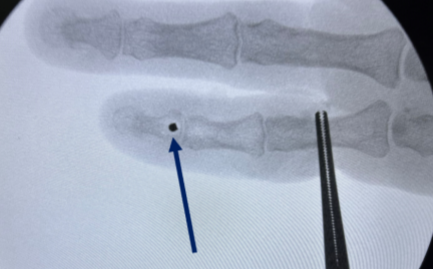

A “Delayed Jersey Finger”: Case Report and Literature Review

Musa Ergin , Süha Ahmet Aktaş